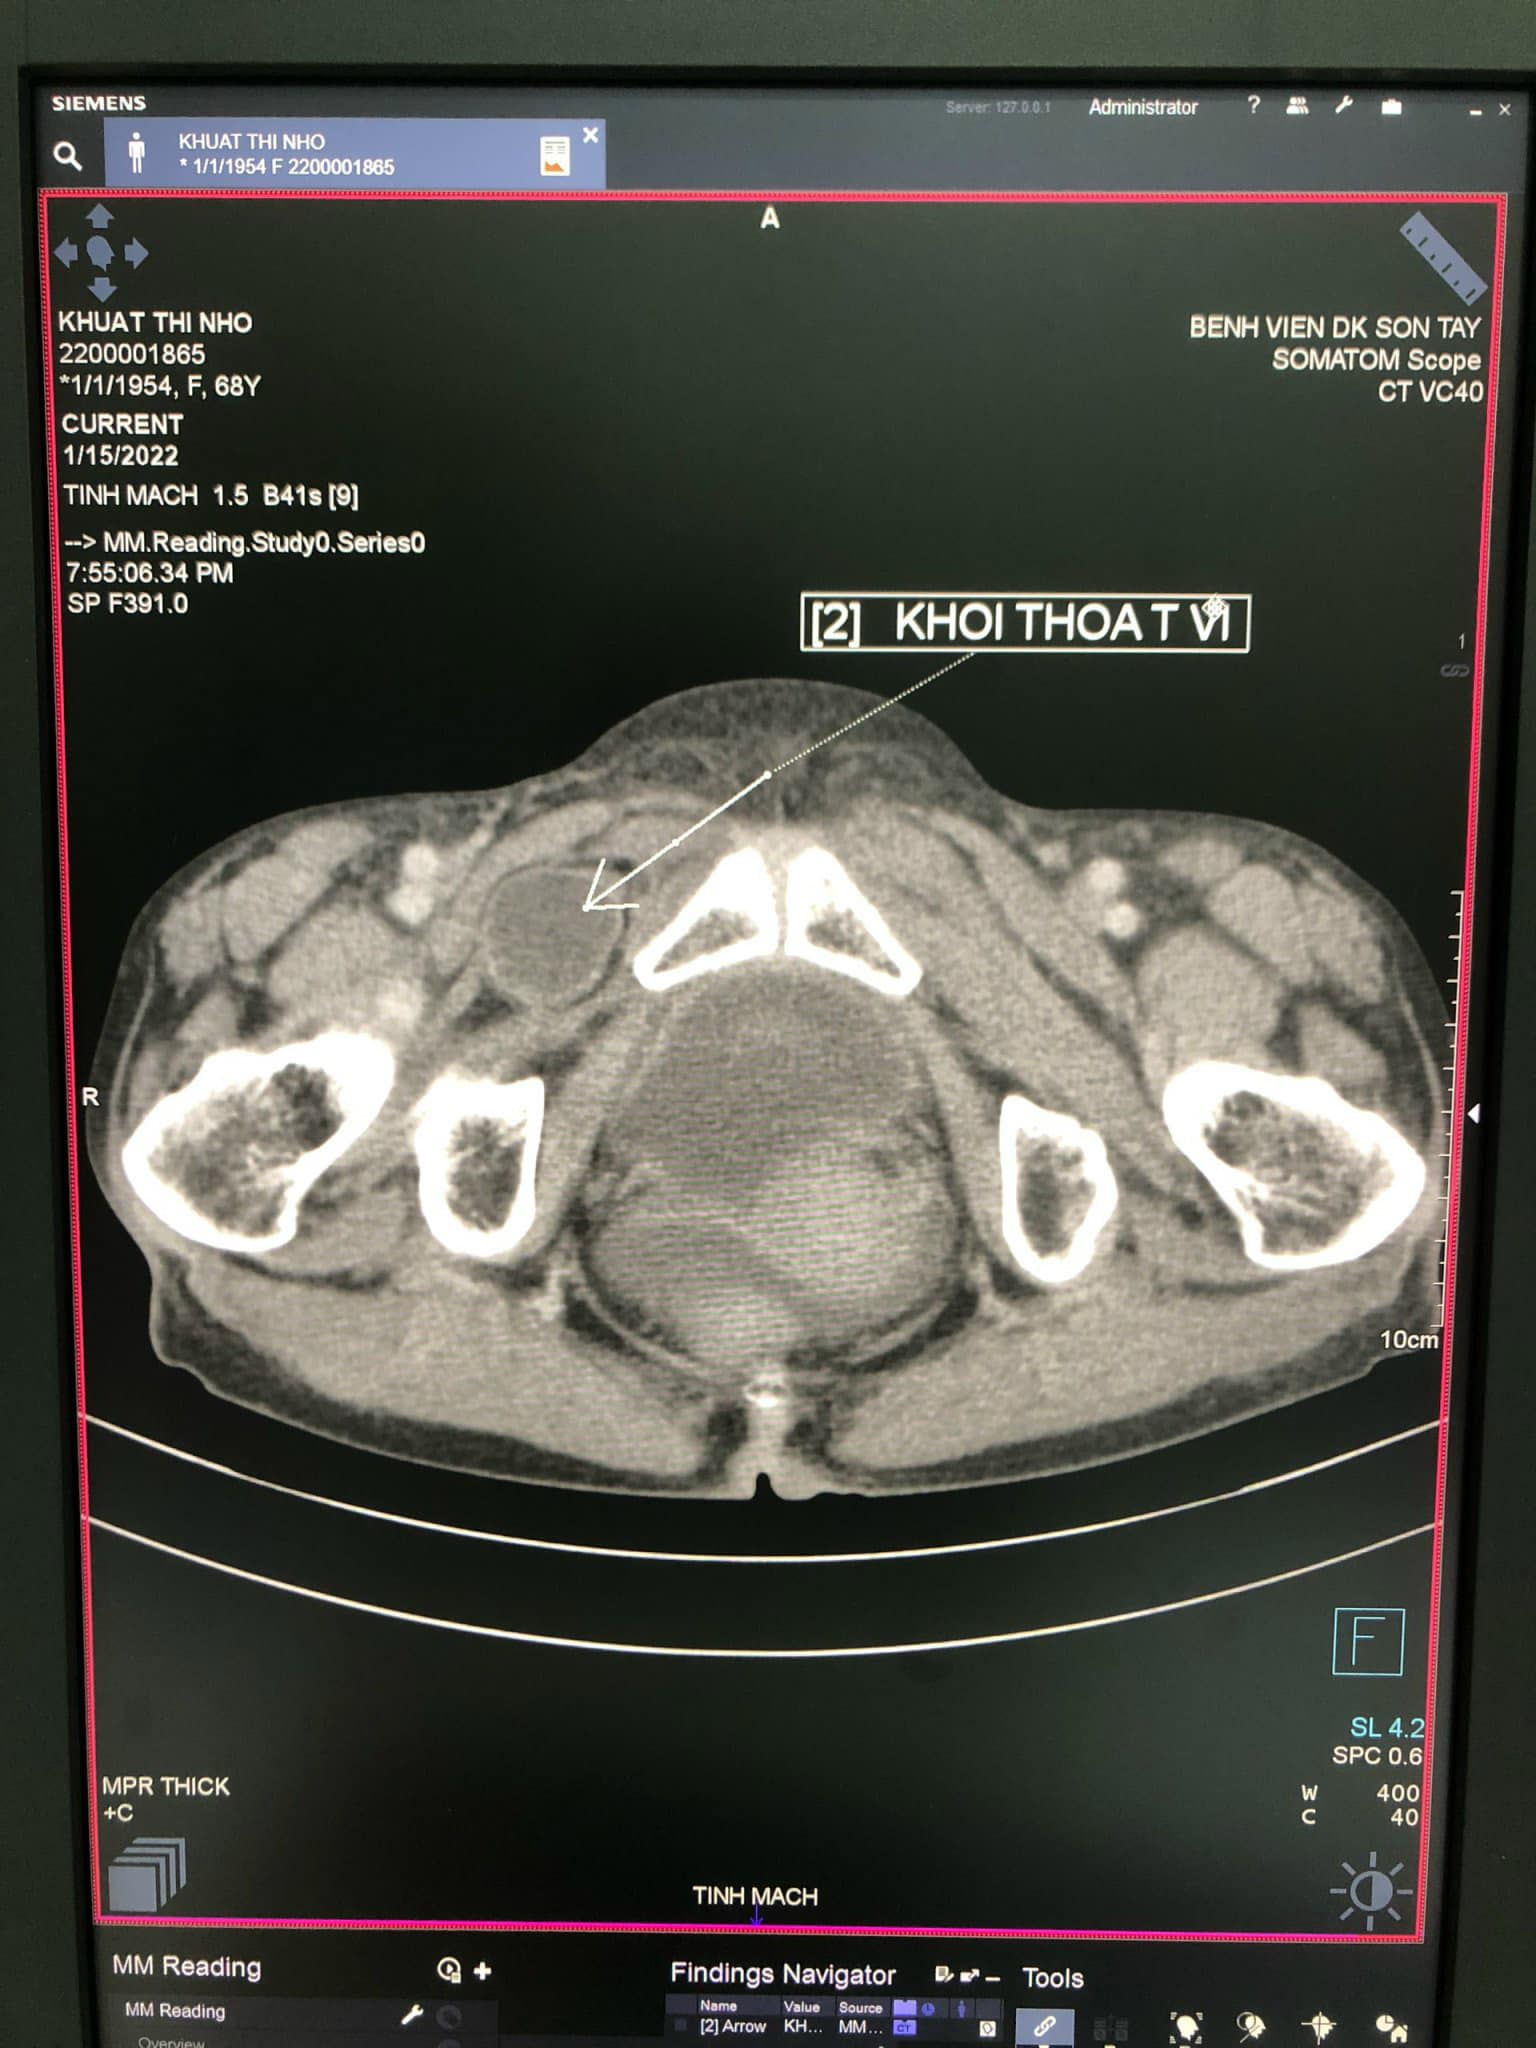

Qua thăm khám, thực hiện chụp cắt lớp vi tính (CT) phát hiện có quai ruột non chui qua và kẹt ở lỗ bịt bên phải, các quai ruột non giãn, đường kính từ 27-30mm. Tiến hành hội chẩn, các bác sĩ xác định bệnh nhân bị thoát vị bịt bên phải nghẹt, chỉ định mổ cấp cứu.

Bệnh nhân Khuất Thị N đã được bác sĩ khoa Ngoại Tổng hợp, khoa Chẩn đoán hình ảnh, khoa Gây mê và Hồi sức cấp cứu Bệnh viện đa khoa Sơn Tây phát hiện và phẫu thuật cấp cứu kịp thời. Quá trình phẫu thuật ghi nhận các quai ruột giãn to, nhiều dịch. Quai ruột cách góc Treizt khoảng 40cm chui vào lỗ bịt bên phải gây hoại tử ruột. Tiến hành giải phóng quai ruột nghẹt, khâu lại lỗ bịt. Cắt đoạn ruột hoại tử, đầu trên cách góc Treizt 20cm xét thấy phải nối ngay không thể làm hậu môn nhân tạo được. Kíp phẫu thuật đã phải nối ruột bên bên luôn.